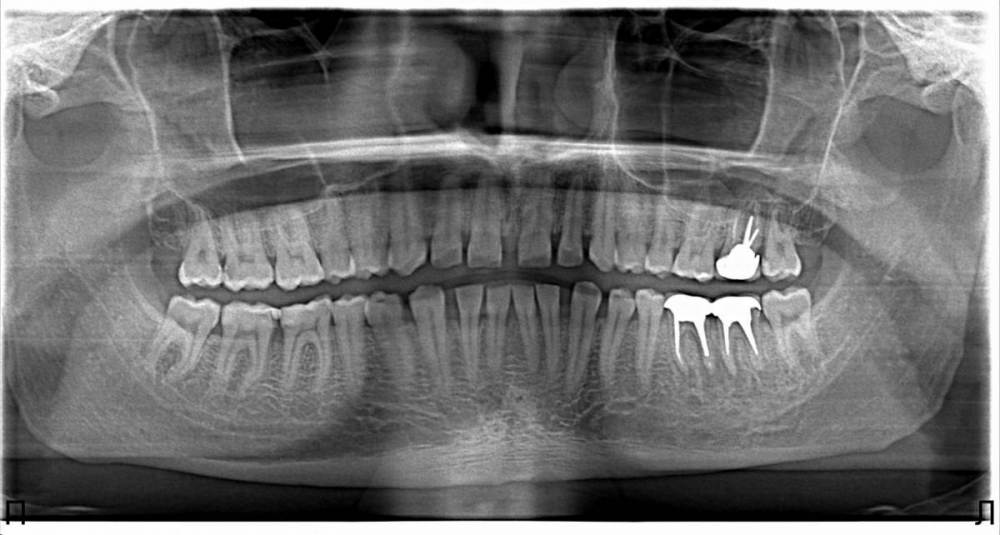

ZubGluposti Опубликовано 30 мая, 2022 Поделиться Опубликовано 30 мая, 2022 Добрый день друзья. Лет 5 назад мне установили коронки. Проблема была в том, что коронки очень скоро разъехались и в них стала забиваться пища и в какой то момент коронка скололась. Была установлена единая коронка на 2 зуба, но и она периодически отваливалась. После последней установки коронки под неё стала забиваться пища и выскочил флюс. Флюс дренировали, но хватило на 2 недели, а теперь я не мог жевать этими коронками. Доктор отказался от лечения мотивируя тем, что зубы очень маленькие и имплант установить не представляется возможным. Предложил длинный мост без гарантии. Сходил сделал снимок и предложили 2 коронки за 200.000р. Прошу у Вас совета как поступить всё таки 200.000р это очень дорого. Ссылка на комментарий

Гарриевич Опубликовано 4 июня, 2022 Поделиться Опубликовано 4 июня, 2022 31.05.2022 в 20:07, ZubGluposti сказал: Спасибо за ваши советы. Нашел в своем городе клинику. За импланты объявили 120.000₽ за 2 штуки. И удаление коронок с вкладками и неприятное выскабливание кисты отдал 12.000₽. Импланты говорит ставить будет через 6 месяцев когда кость нарастет. Возможно и не стоит удалять. У вас есть ещё какие нибудь снимки? Ссылка на комментарий